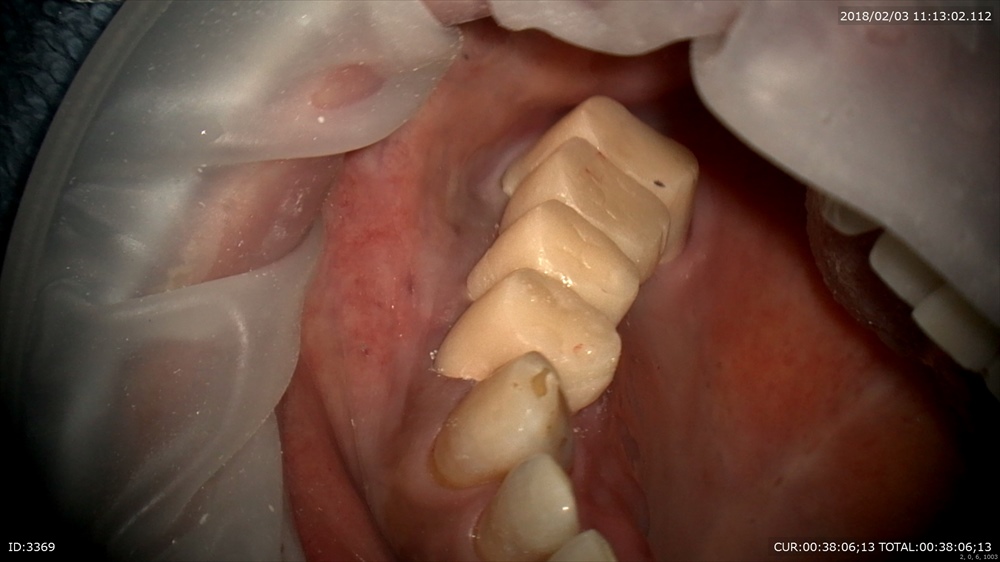

次も虫歯 歯に物がつまる。

これは。

われています。この様に虫歯は「力」によって起こることがあります。

クラック。ヒビがおきてそこから細菌の進入し

このように

大きな虫歯を内部で作ります。だからただ虫歯ができたら詰めるその行為では駄目で原因を探り力のコントロールを行います、そうでないと原因が断ち切れていないので同じ事がおきます。

深くても

MTAセメント

OK

型取りして次回で終了。